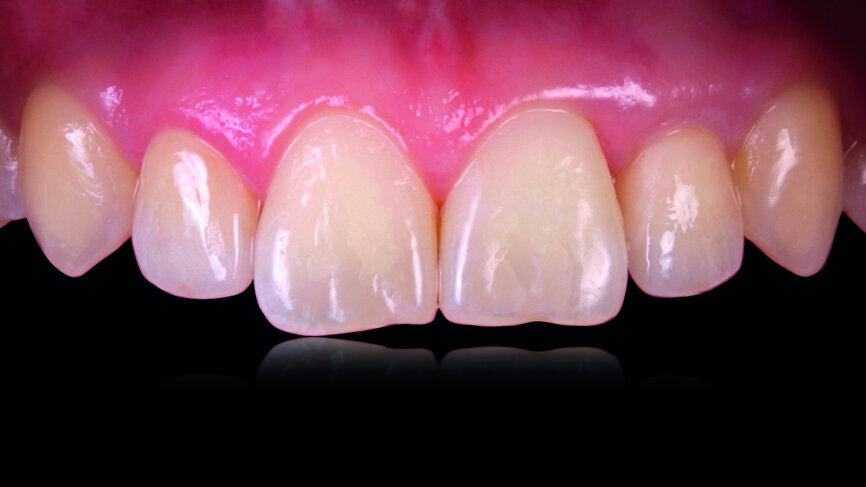

The clinical case features a female patient, who complained about missing tooth #22, as well as the shield-like shape of tooth #12 (Figs. 1 & 2). During the initial examination, the area around the missing tooth was estimated to be quite narrow for an implant. However, the patient declined orthodontic preparation, as she had already previously had orthodontic treatment with orthodontic surgery.

Fig. 1: The patient’s upper teeth before treatment.

Fig. 2: The patient’s upper teeth before treatment.